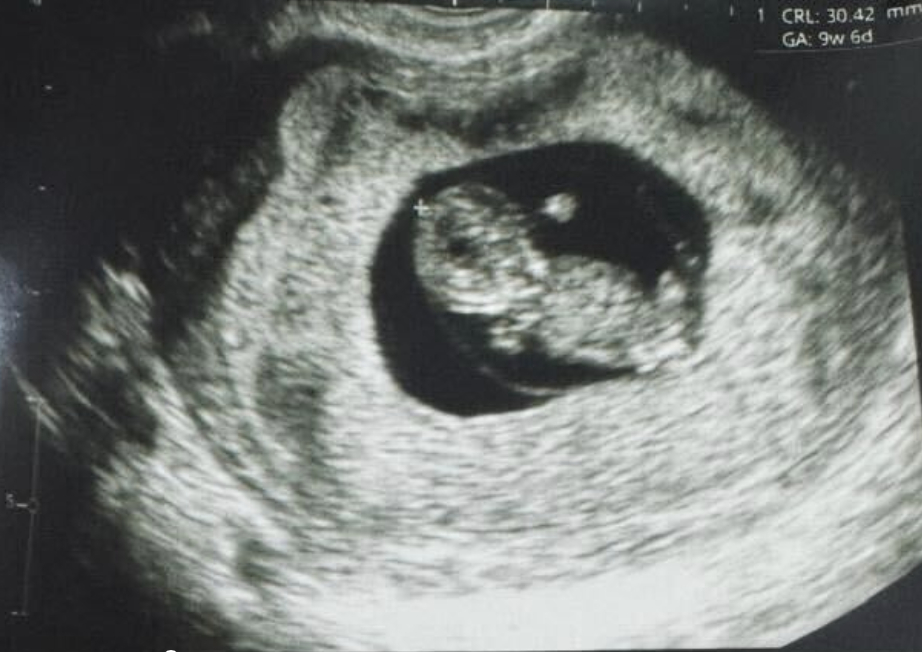

全球首例:使用誘導(dǎo)多能干細(xì)胞體外成熟卵子技術(shù),成功產(chǎn)下一名嬰兒

紐約(?BUSINESS WIRE?)致力于推動(dòng)女性健康治療方案發(fā)展的生物技術(shù)公司Gameto與2024年12月16日宣布,該公司利用 Fertilo 實(shí)現(xiàn)了全球首例活產(chǎn)。此次分娩在秘魯利馬的圣伊莎貝爾診所進(jìn)行。